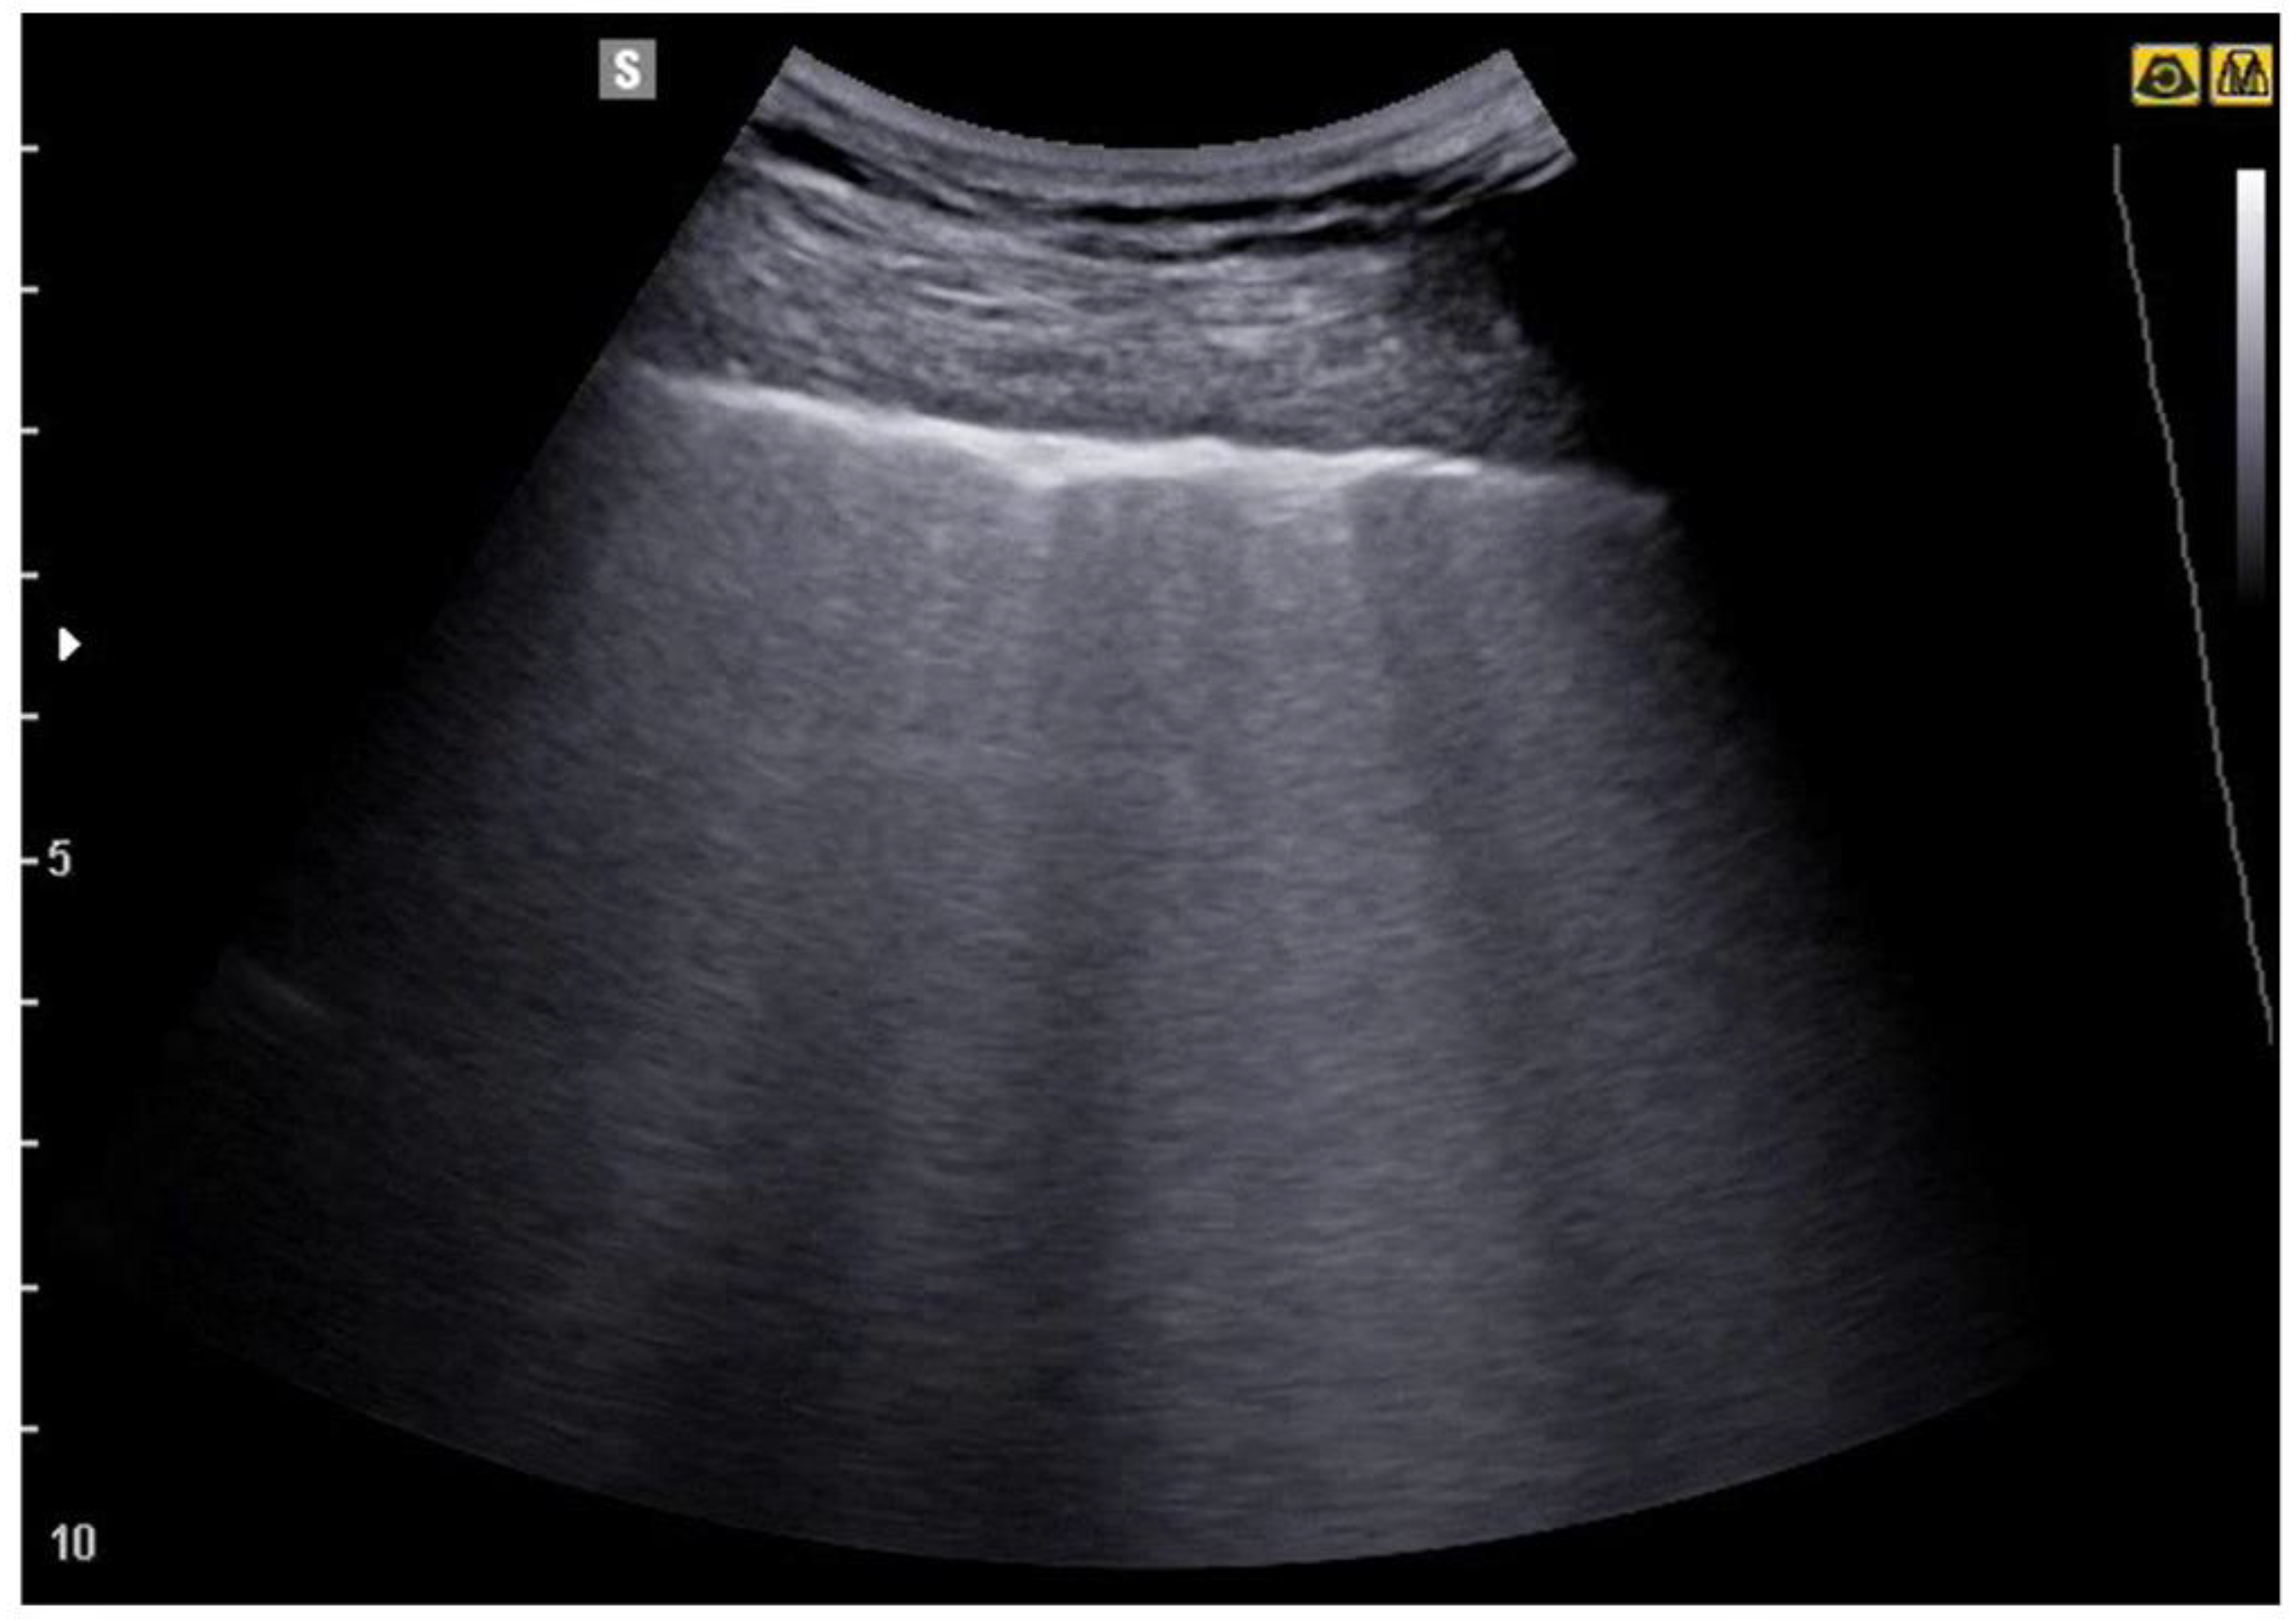

4. Lung Ultrasound on Physiological Lung